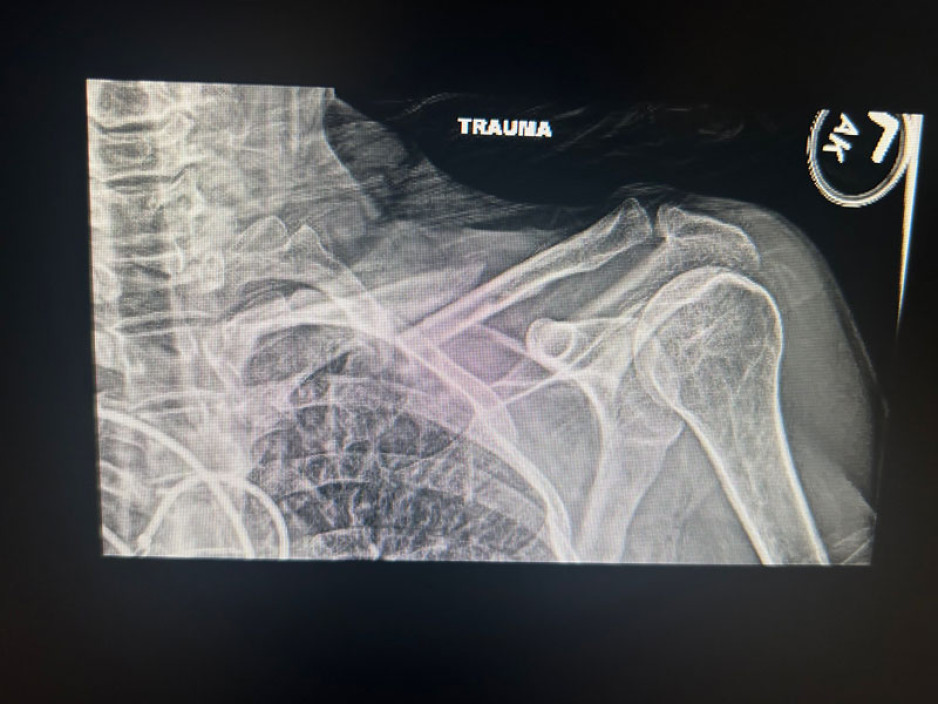

The next thing she remembers is waking up in an ambulance with broken ribs and collar bone and a serious concussion.

X-rays from Janet Tufts with a legend that says: "Trauma"